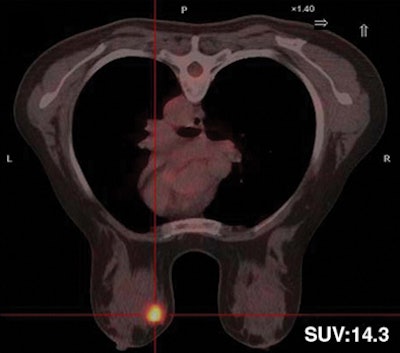

| Thirty-two-year-old woman with ductal infiltrating adenocarcinoma measuring 18 mm in maximum transverse diameter. Axial fused PET/CT images obtained with patient in prone position at time point 1 (above) and time point 2 (below) show corresponding standard uptake values. |